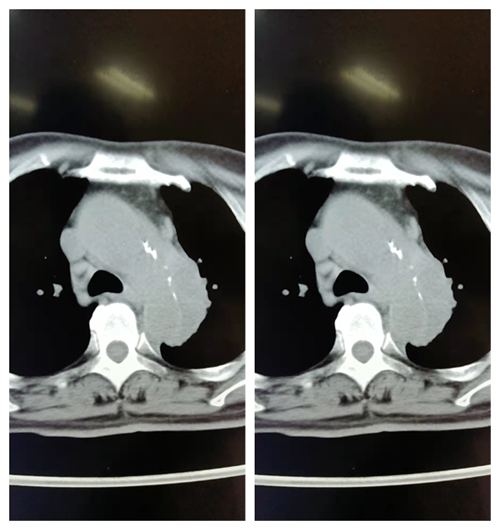

患者贾大爷两周前因突然胸疼前来检查,在肺平扫图像中,CT医师李光喆凭借高度专业敏感性和多年经验发现主动脉的异常,这一异常引起了李光喆的重视,建议立即进行主动脉CTA进一步检查,检查结束后李光喆立即与科室医生进行会诊,判定这是一个主动脉穿通溃疡的患者,英文名PAU ,病灶很大,如不及时手术会有生命危险 。CT大夫第一时间通知了临床医生和患者家属,患者及时住院进行手术治疗,保住了生命。患者及家属心情激动,无法用言语表达对CT大夫的感激之情,为影像科送来一面锦旗。